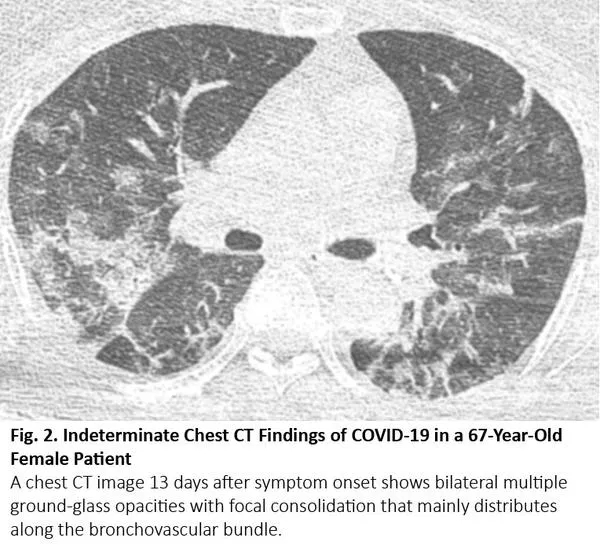

COVID-19的胸部CT可伴有局部的实质化和网状阴影(铺路石征影像表现)或其他组织性肺炎的表现,如反晕征。17% - 20%的COVID-19患者的CT与各种感染性、非感染性肺部疾病(如超敏性肺炎、肺孢子虫肺炎和弥漫性肺泡出血)难以区分(图2)。

图2. 一位67岁女性患者的胸部CT呈现COVID-19不典型特征